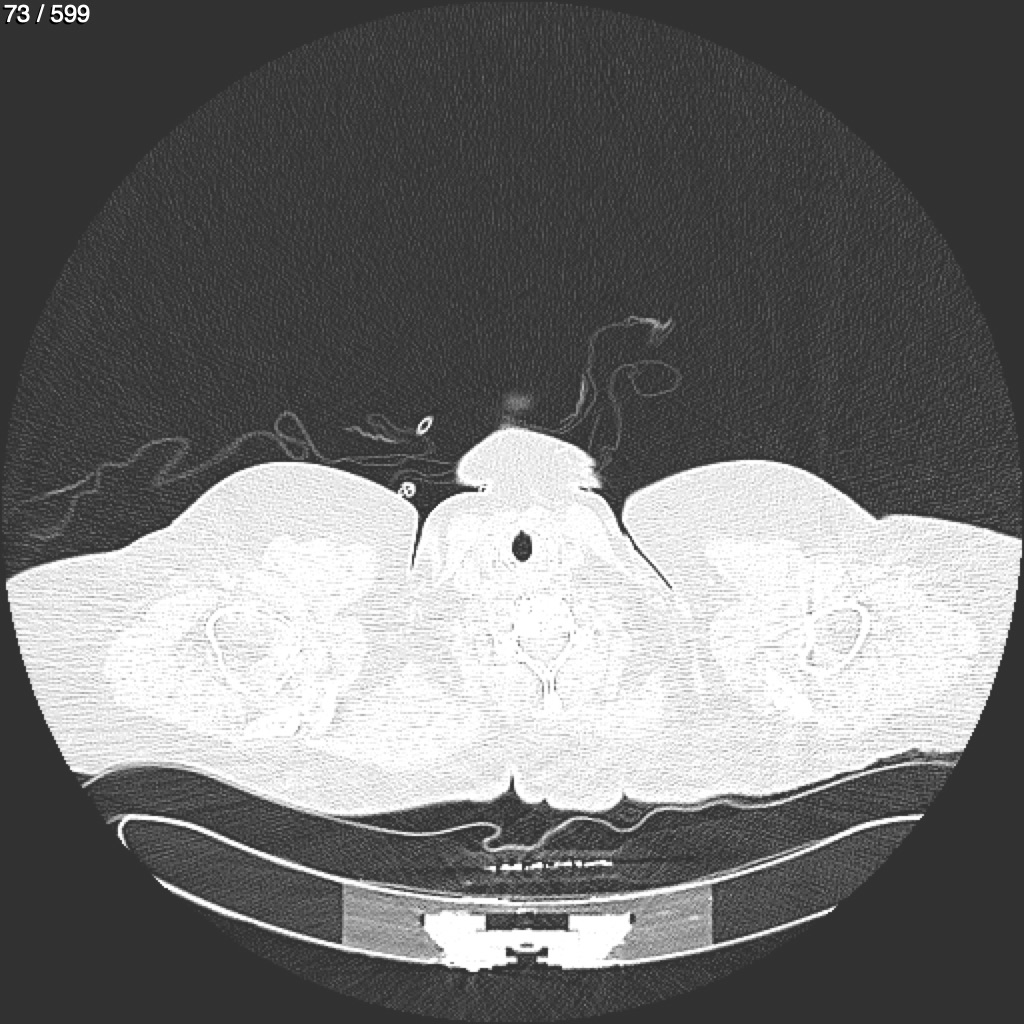

Home G​l​o​r​i​a​ ​G​l​a​d​y​s​ ​B​e​a​s​l​e​y​ ​-​ ​T​ó​r​a​x​ ​T​o​r​a​x​_​S​i​m​p​l​e​ ​(​A​d​u​l​t​o​)